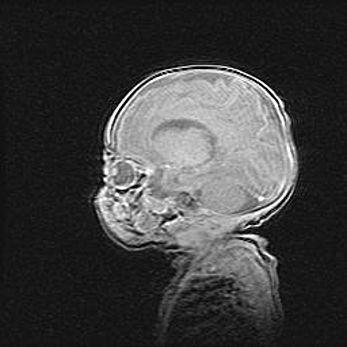

Сообщающаяся гидроцефалия. Кистозная энцефаломаляция головного мозга.

Возраст: 3 месяца 4 дня

Вес: 3100 г

Пол: женский

Окружность головы: 34 см

Срок гестации: 31 неделя

Кистозная энцефаломаляция головного мозга - одна из форм поражения головного мозга в детском возрасте. Характеризуется возникновением множественных и распространённых кист в коре, белом веществе и подкорковых образованиях головного мозга у плодов, новорождённых и детей раннего возраста. Развитие кистозной энцефаломаляции связано с внутриутробной асфиксией и гипотонией, родовой травмой, тромбозом синусов, пороками развития сосудов, инфекциями, сепсисом и другими причинами. Наиболее значимые инфекционные агенты: вирусы простого герпеса, цитомегалии, краснухи, токсоплазмы, энтеробактерии, золотистый стафилококк и другие.